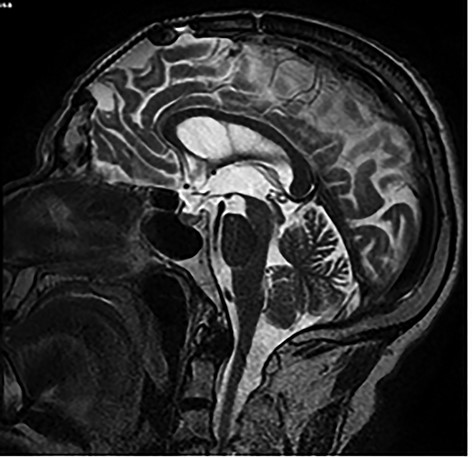

Brain MRI showing titanium cranioplasty without signs of relapse.

and cranioplasty was performed. No clinical or imaging signals of recurrence had been described. We requested a new brain magnetic resonance imaging (MRI) concluding that there was no tumour recurrence (Fig. 3).

In most cases the medical history was not relevant, except for one case, in which a 10-year-old child was diagnosed with a mandibular meningioma and 2 years after the tumour enucleation, he showed odontogenic keratocytes due to basal cell nevus syndrome. Some other cases had a history of dental treatments. In our case, medical history was important because he had an intradiplocal meningioma treated 16 years ago. We made sure that there was no relationship with the current meningioma, with no signs of recurrence shown on MRI.